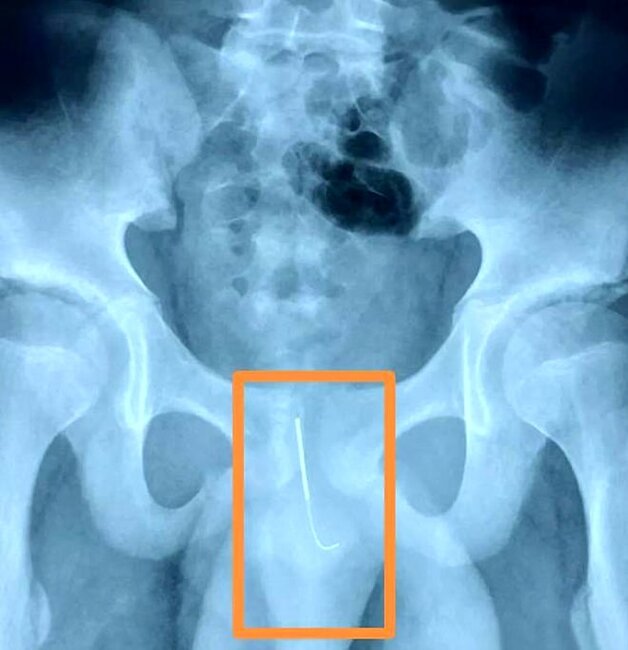

Uşaq cinsiyyət orqanına 11 sm-lik iynə salaraq gecə yuxusuz qalmağa çalışıb. Səhəri gün anası uşağın yeriməkdə çətinlik çəkdiyini görüb və onu xəstəxanaya aparıb.

Müayinə edilən zaman iynənin 15 saata yaxın müddətdir uşağın cinsiyyət orqanında olduğu müəyyənləşib. İki saat çəkən əməliyyatdan sonra iynəni çıxarmaq mümkün olub.